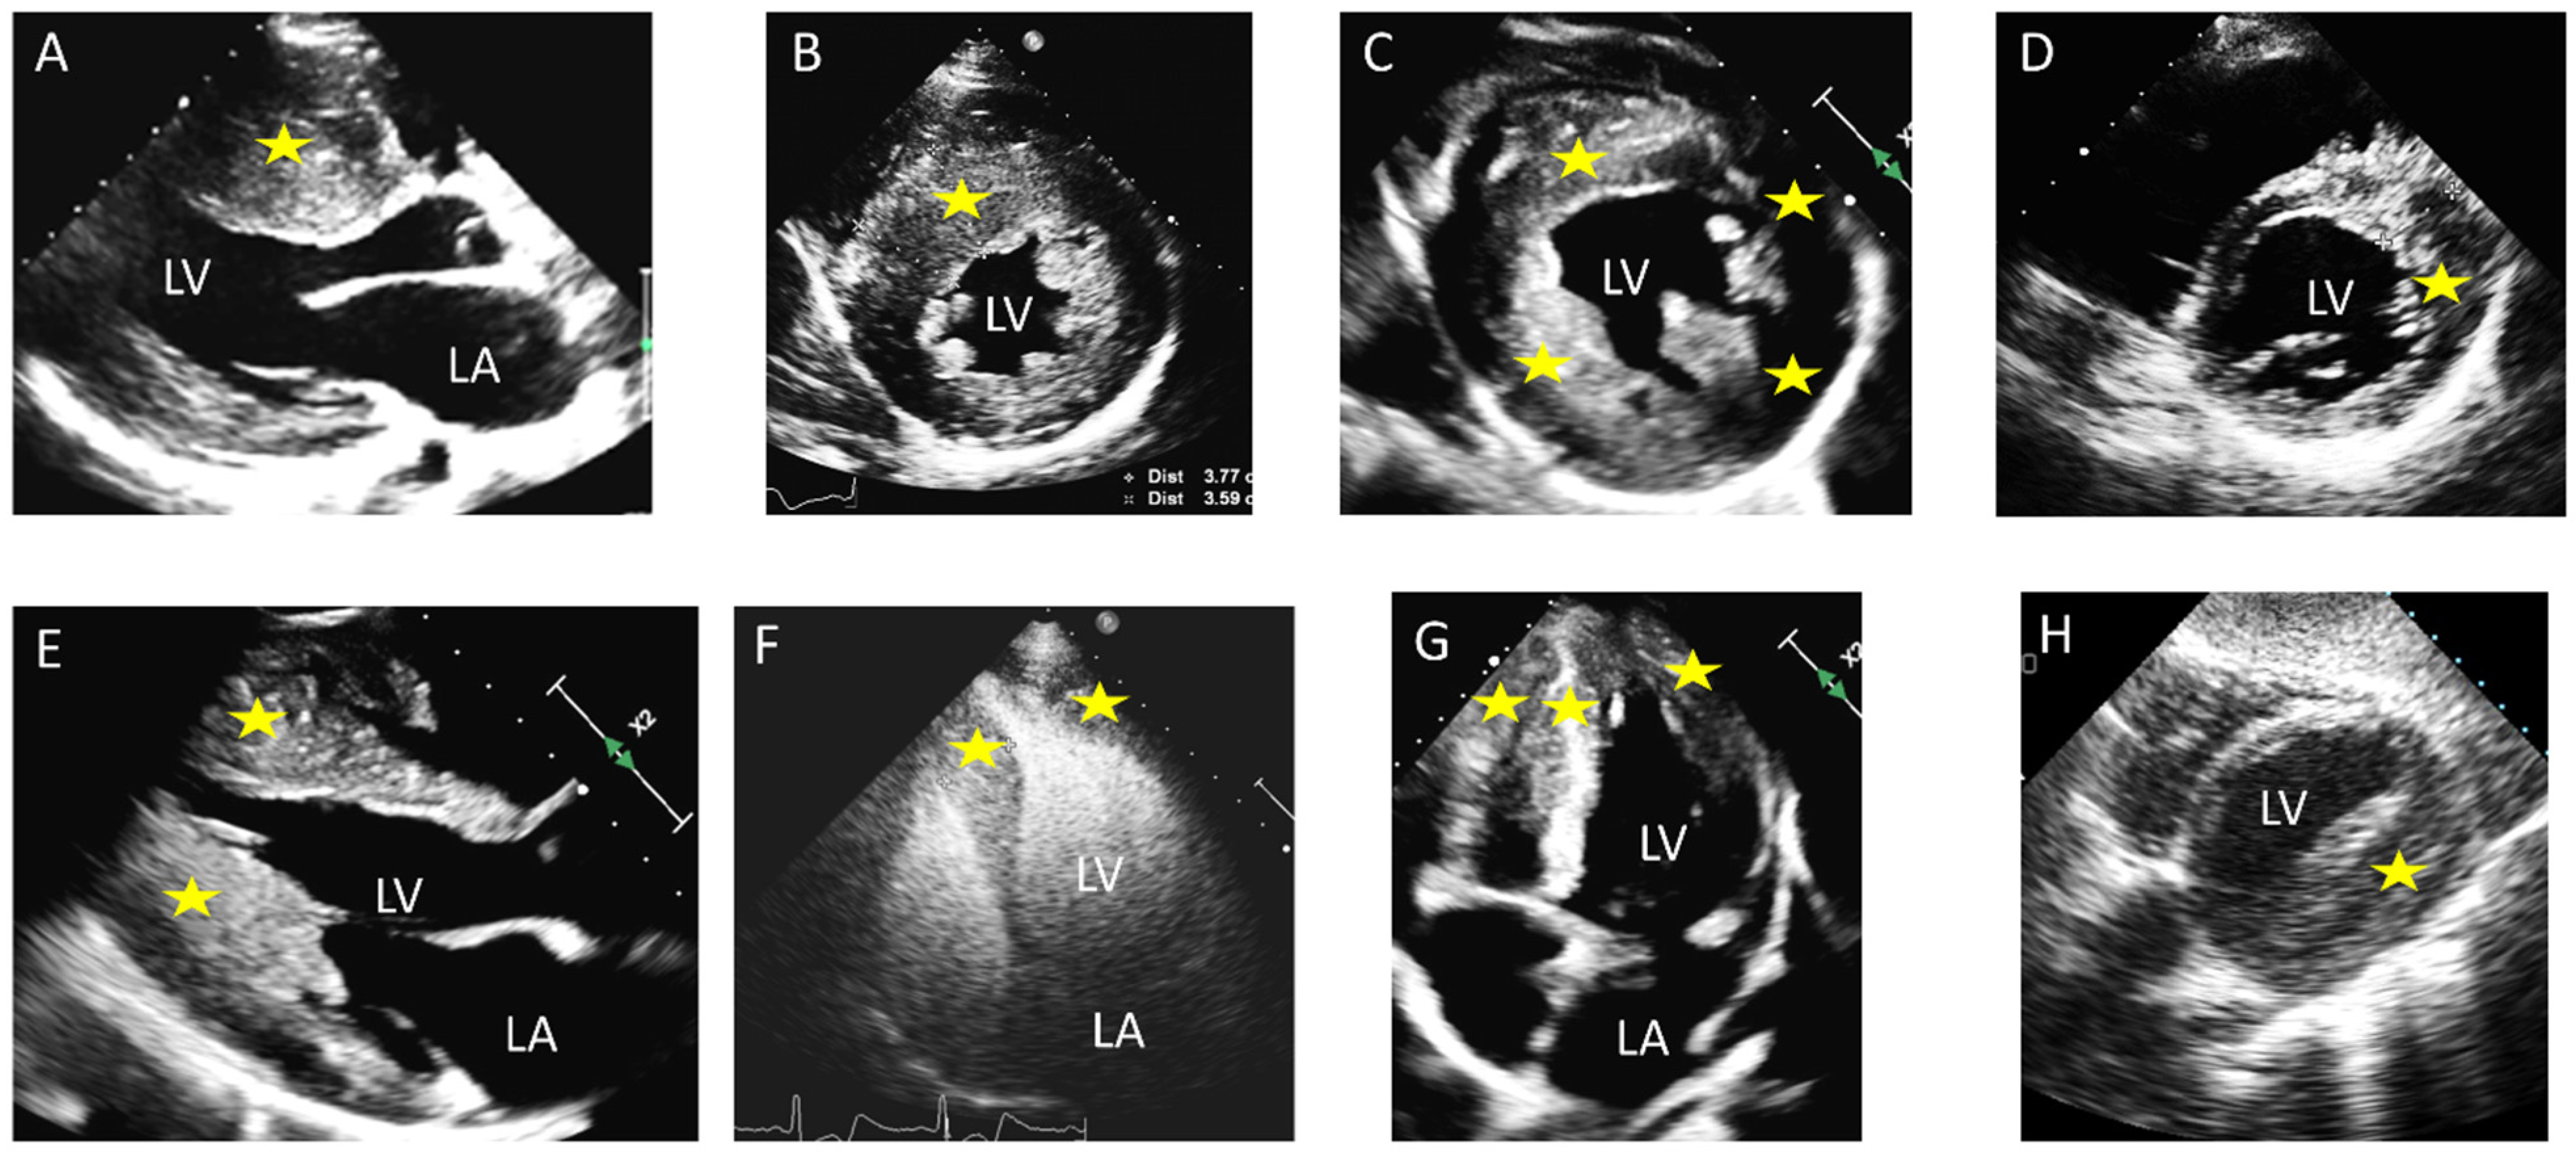

2. Distribution of Segmental Hypertrophy

| Echocardiography | Septal hypertrophy; LVOT obstruction; SAM of the anterior mitral leaflet ± SAM-associated mitral regurgitation | Uniform thickening of LV walls; no LVOT obstruction typically | Apical wall thickening; “ace-of-spades” morphology of the LV cavity; ±apical aneurysm |

| Hemodynamics | Dynamic LVOT obstruction present in the obstructive form; diastolic dysfunction; mid-ventricular obstruction may be present | Diastolic dysfunction; usually no LVOT obstruction. | Diastolic dysfunction; no LVOT obstruction; mid-ventricular obstruction frequent |